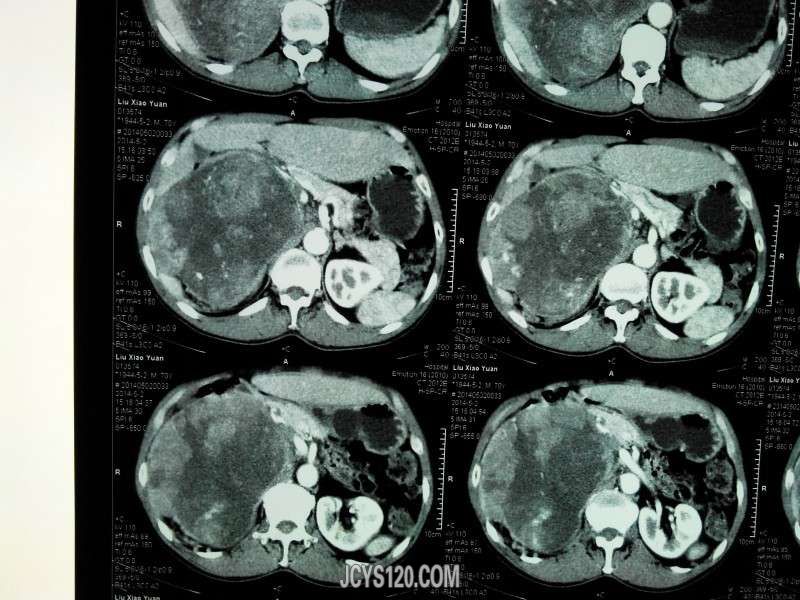

患者女性,70岁,体检发现,大家诊断什么病,怎么治疗。谢谢!